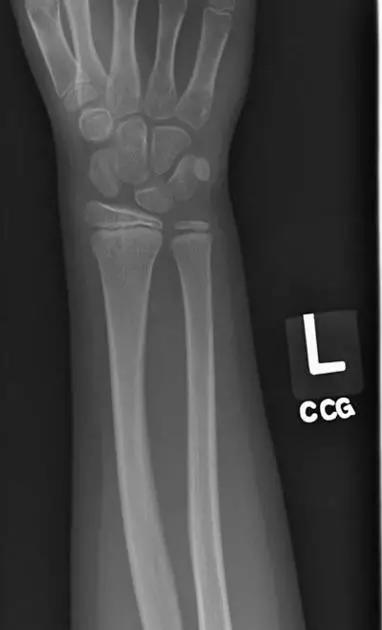

2. Colles 骨折

桡骨远端骨折,伴有桡骨远端向背侧的移位,可以有或没有尺骨干的骨折。具有这几个特征:背侧粉碎、向背侧成角、向背侧移位且挠骨短缩的关节外骨折。

典型 colles 骨折,枪刺样、餐叉样畸形